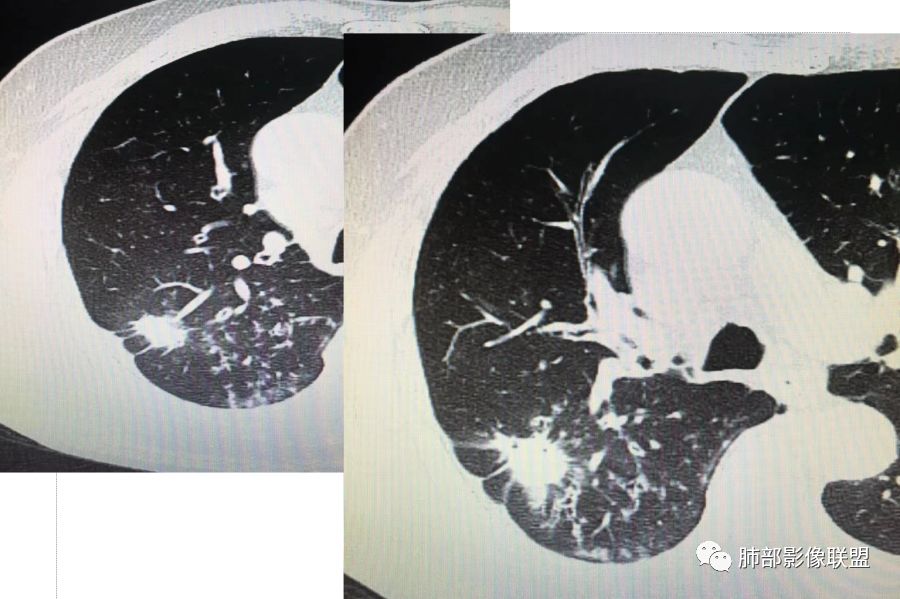

胸CT示病变位于右肺上叶,右肺上叶前段支气管壁不规则增厚狭窄、远端扩张。右肺上叶后段实变影,纵隔窗实变内可见钙化灶,可见支气管引流征,引流支气管壁明显增厚,边缘可见短硬毛刺,胸膜牵拉,u型征,周围可见卫星灶,并可见支气管扩张及其管壁增厚;病灶整体存在膨胀性生长。考虑良性病(结核)变基础上合并癌变,腺癌?

患者中老年男性,咳嗽喘息半年。查体双肺闻及哮鸣音。胸部CT:右肺上叶后段不规则结节灶,可见长毛刺、胸膜牵拉、分叶及钙化征象,周围见点片状卫星灶,近端支气管壁增厚,呈支气管爬行征。综合考虑结核。鉴别恶性病变。

老年男性,咳嗽半年,右肺上叶后段实性结节伴粟粒状卫星灶,结节内有钙化,部分边缘平直,周围见长索条,有胸膜牵拉,结核是明确的,常规需要增强判断有无合并肺癌,当然该患者已经穿刺。

右肺上叶后段结节,点状钙化,边缘见细长毛刺,胸膜凹陷,卫星灶伴树芽症,支气管壁增厚扩张,有截断,考虑结核,但腺癌没法排除,确实有增强就基本能明确。

右肺上叶后段结节,长毛刺、钙化灶、近端小空洞、索条影、周围支气管树丫、引流支气管增厚,主体病灶侧后方分隔样空腔,弥漫支气管增厚,大气道受累,支持感染的征象较多,TB、曲霉;分叶、膨隆、脊状凸起、毛刺等恶性征象也有,遗憾没看到增强,只有期待活检一槌定音。

老年男性,咳嗽半年,右肺上叶后段实性结节,内见钙化,边缘部分膨隆,有长短毛刺、分叶、空泡征,胸膜侧见胸膜牵拉,周围不干净,见小卫星灶,右上叶后段支气管管壁增厚,扩张,有炎性及恶性征象,一元论常规考虑炎性肉芽肿病变,结核可能,腺癌不除外,二元结核并腺癌,建议增强及穿刺活检。

右肺上叶后段团块影,内见钙化,周围胸膜有牵拉,近段支气管扩张管壁增厚,周围可见卫星灶,右支气管狭窄,综合考虑支气管内膜结核,鉴别真菌感染(气道侵袭性曲霉菌病)。

右上后段结节,整体收缩,长软毛刺丶胸膜凹陷,有点状钙化丶小空洞,引流支气管明显管壁增厚,周边卫星灶明显,有喘息史半年,可能有应用激素史,致内源性复发,考虑TB,鉴别腺癌。

3.本例病灶影像表现为:右肺上叶后段不规则结节灶,病灶整体存在膨胀性生长,可见毛刺、胸膜牵拉、分叶及钙化征象,近心端小空洞,周围见点片状卫星灶并出现磨玻璃影,近端支气管壁增厚,管腔扩张,既有恶性征象,也有结核的征象。南边老师考虑结核与腺癌同时存在,但遗憾的是缺乏增强扫描图像,亦未提供结核相关辅助检查结果。